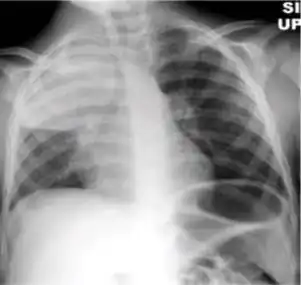

Dense homogenous opacity in right, middle and lower lobe of primary pulmonary TB. -

Chest x-ray showing patchy opacification on the upper right and mid-zone lung with fibrotic shadows, as well as bilateral hilar lymphadenopathy. -